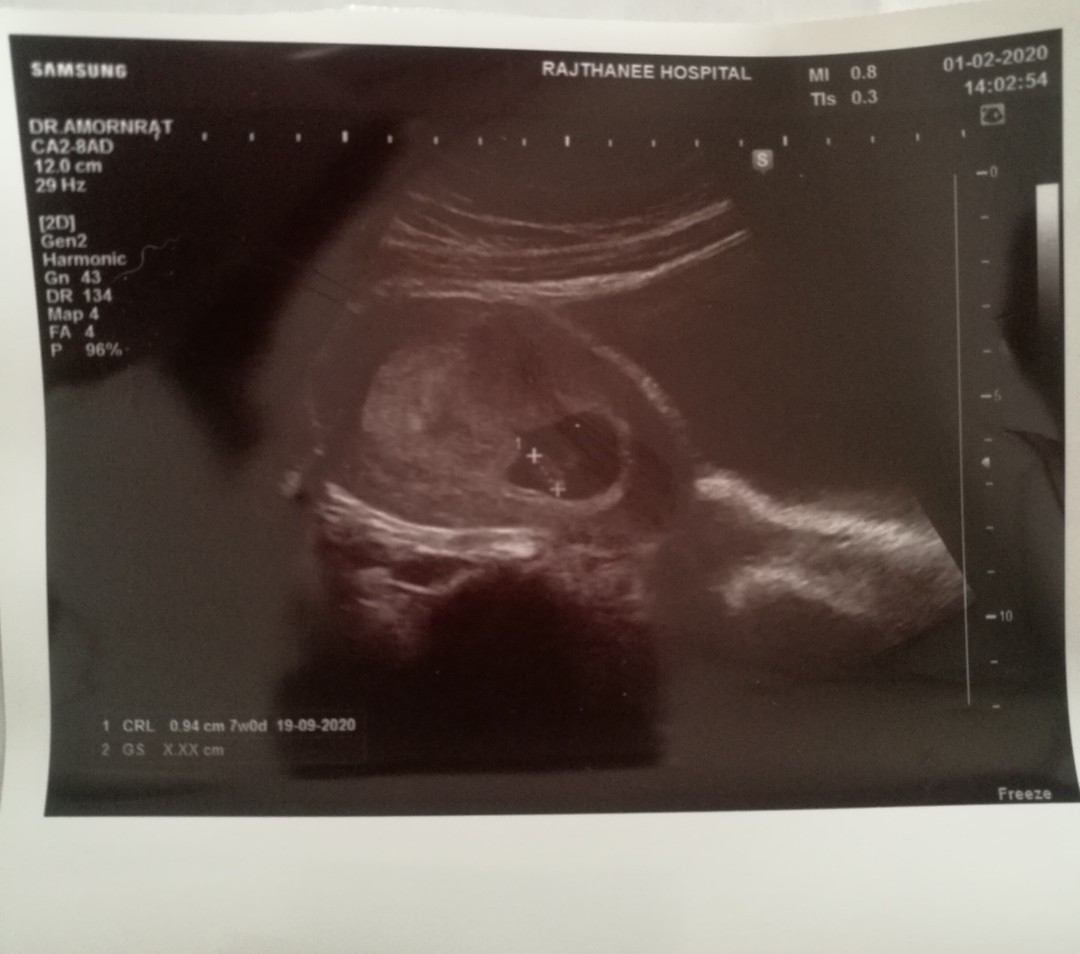

ตอน 8 วีคค่ะ

ตอน 8 วีค คุณหมอบอกยังเห็นไม่ชัด ตอนนี้ 13 วีค เต้นปกติค่ะ